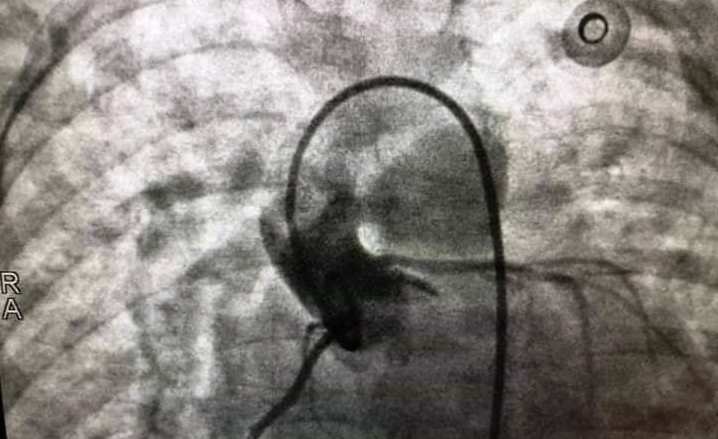

Kỹ thuật can thiệp tim mạch được thực hiện bằng cách luồn dụng cụ vào mạch máu bệnh nhân, qua đó, đưa dụng cụ đến tim để bít các lỗ thông ở trong tim hoặc nong rộng những chỗ hẹp ở van tim hoặc mạch máu. Ths. Bác sĩ Lê Anh Minh, Phó Trưởng khoa Tim mạch- lồng ngực, Bệnh viện Nhi Thanh Hóa là người đầu tiên có công trong việc đưa phương pháp can thiệp này về cho bệnh nhân nhi ở Thanh Hóa.

Phương pháp can thiệp được thực hiện bằng cách luồn dụng cụ vào mạch máu bệnh nhân, qua đó, đưa dụng cụ đến tim để bít các lỗ thông ở trong tim hoặc nong rộng những chỗ hẹp ở van tim hoặc mạch máu.